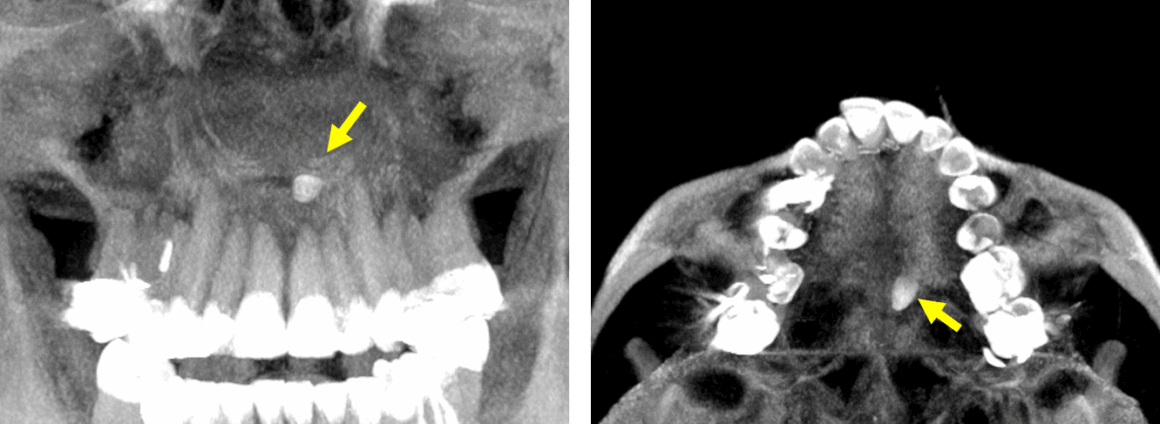

Fig.1

En la evaluación tomografía computarizada cone beam, se realizaron los cortes sagitales (Fig.1) la presencia de un objetó de densidad dentaria a nivel de la placa horizontal del hueso palatino, que se articula con la apófisis palatina del maxilar superior, que compromete la cortical superior e inferior.